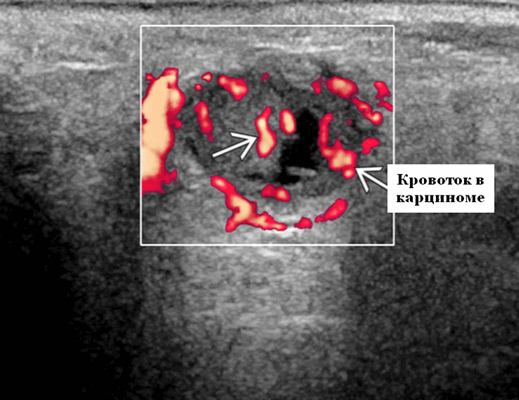

Цветной допплер. Цветной допплер: выраженная внутриопухолевая васкуляризация. Спектральный допплер: повышенное внутрисосудистое сопротивление. Индекс сопротивления> 0,8, индекс пульсации> 2,0

Энергетический допплер. Внутриочаговая васкуляризация. Хаотический / дезорганизованный или преимущественно периферический кровоток

- Интранодулярный кровоток хаотичный / дезорганизованный или преимущественно периферический